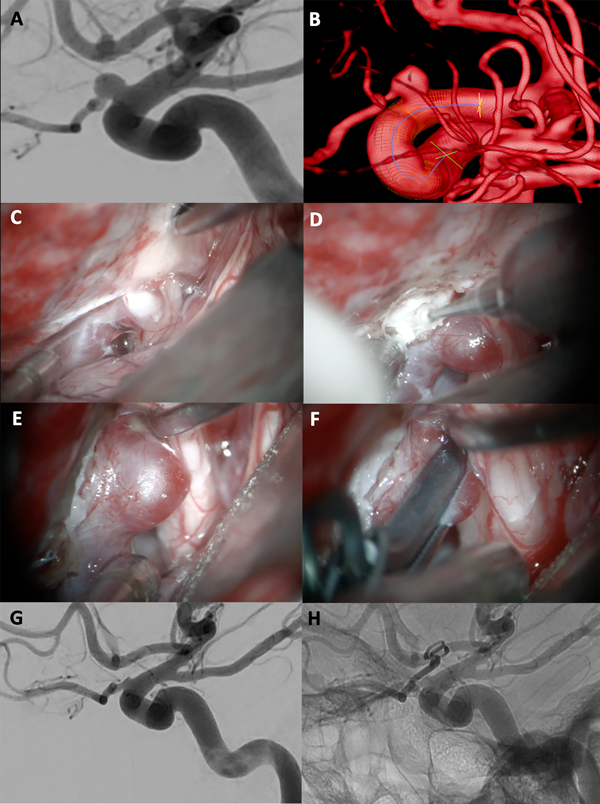

Figura 4. A-B: Se aprecia una arteriografía cerebral con reconstrucción tridimensional que evidencia un aneurisma carótido oftálmico izquierdo, nótese como la arteria oftálmica sale del domo del aneurisma. C-F: Fotografías intraoperatorias. Observamos la cisterna óptico-carotidea donde es visible el saco aneurismático ejerciendo gran efecto de masa sobre el nervio óptico. Posteriormente se realizó una clinoidectomía anterior parcial logrando una adecuada exposición del cuello del aneurisma. Se muestra la exclusión del aneurisma con un clip angulado. G-H: Imágenes de arteriografía cerebral post operatoria que evidencia la exclusión completa del aneurisma con preservación de la arteria oftálmica.

Figura 5. A-B: Se aprecia una arteriografía cerebral que evidencia un aneurisma carótido oftálmico izquierdo gigante. C-F: Fotografías intraoperatorias. Observamos la cisterna óptico-carotidea donde es visible el saco aneurismático ejerciendo gran efecto de masa sobre el nervio óptico, no es visible la arteria carótida. Posteriormente se realizó una clinoidectomía anterior total y sección del anillo dural distal logrando una adecuada exposición del cuello del aneurisma. Se muestra la exclusión del aneurisma con dos clips rectos. G-H: Imágenes arteriografía cerebral post operatoria que evidencia la exclusión completa del aneurisma con preservación de la arteria oftálmica.